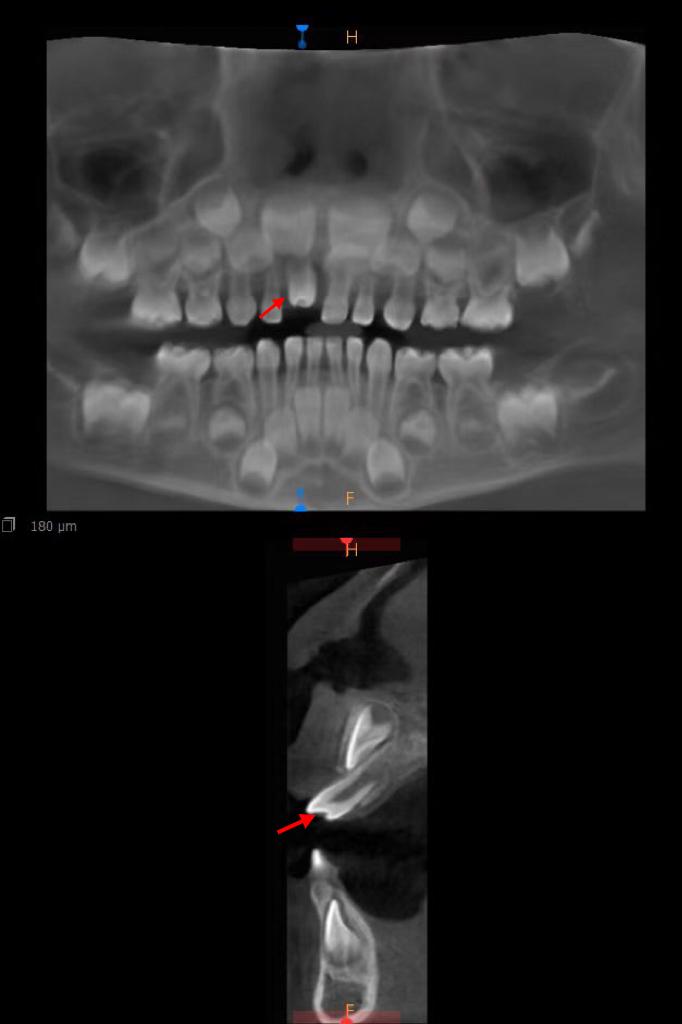

箭头所示为倒置生长的埋伏多生牙

接诊的何孔炎主任医师在仔细检查后发现,这颗新牙极有可能是一颗多生牙。经家长同意,医院立即为孩子进行了口腔三维CT检查。结果证实了医生的判断:这颗形态异常的牙齿确为多生牙,而本该在此萌出的正常恒牙胚,正被它“压制”在下方。

箭头所示为已萌出多生牙

更为惊人的是,CT影像还揭示了另一个隐藏的“秘密”——在患儿左侧门牙牙根舌侧,竟还倒置生长着另一颗埋伏的多生牙。这颗牙齿犹如一颗“定时炸弹”,向上生长,极可能影响未来恒牙的正常萌出。